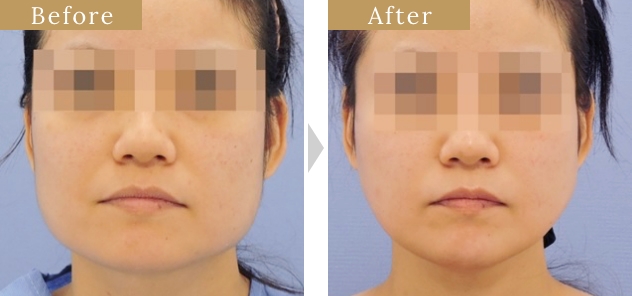

症例

症例

症例